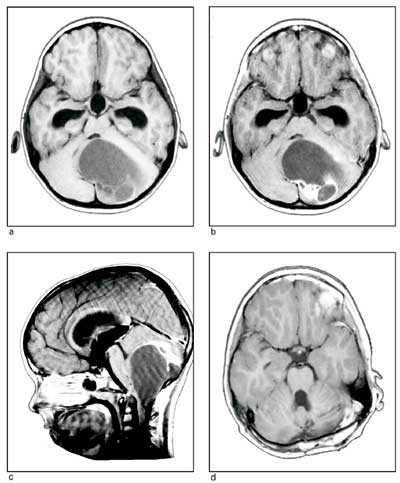

Medulloblastomer er udifferensierte nevroepiteliale svulster(primitiv nevroektodermal tumor, PNET) i lillehjernen, oftest nær midtlinjen (fig 2). De er høymaligne og har uttalt tendens til spredning i subaraknoidalrommet via cerebrospinalvæsken. Tilsvarende svulster i storhjernen kalles nevroblastomer, i corpus pineale pineoblastomer.

Medulloblastomer

Disse sprer seg via hjernevæsken til hele det kraniospinale rom (fig 2). Behandlingen må derfor rettes mot hele nevroaksen og består derfor i å fjerne så mye som mulig av svulsten, deretter gis kjemoterapi og kraniospinal strålebehandling hvis barnet er over tre år (10, 13, 17, 21). Femårs og tiårs overlevelse med dette behandlingsregimet er i Norge henholdsvis 53 % og 45 % (7). Tilsvarende er rapportert fra andre sentre (10, 22). Ingen kan kureres med kirurgi alene (7, 23). Barn under tre år får et intensivt kjemoterapiregime etter operasjonen.

Om lag halvparten av de kurerte får betydelige senfølger av strålebehandlingen, spesielt de som er bestrålt før femårsalderen. Den typisk alvorlig stråleskadede er mentalt redusert, kortvokst, har forsinket kjønnsutvikling, dårlig hårvekst og er sosialt isolert (7). Det forskes på å utvikle kjemoterapiregimer som kan erstatte kraniospinal bestråling. Preliminære resultater gir grunnlag for optimisme ved behandling med kjemoterapi alene (17).